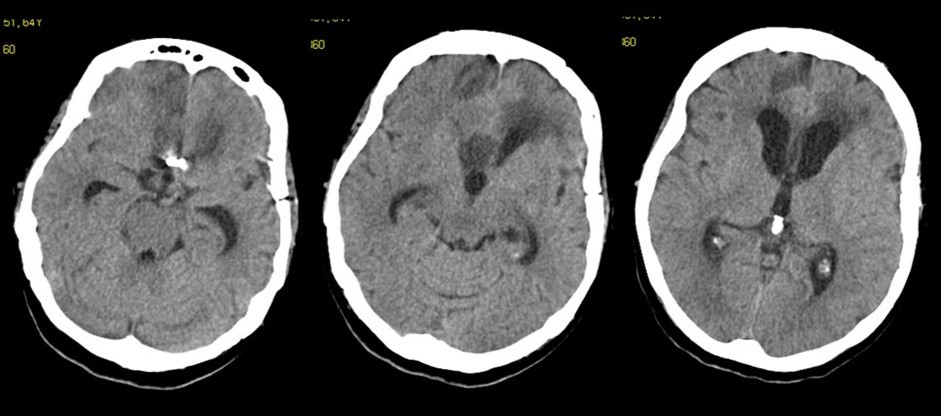

Figure 2.Follow-up at 6 weeks. The vascular clip is in place. Ventricles are quite enlarged. The region of the corpus callosum appears altered

The follow-up CT scan made two weeks later showed a mild ventricular enlargement and persistent density alterations in the frontal region (Figure 2) that were interpreted as normal. Once discharged at home, the patient developed progressive disorientation that finally let her refer to our hospital for consult four months after aneurysm clipping. The cerebral CT we performed showed further ventricular growth, and a tumor-like image in the right frontal lobe (Figure 3). She was admitted to our ward and underwent a contrast-MRI that confirmed the suspicion of aggressive intra-axial neoplasm (Figure 4). The week after, under general anesthesia we performed a right craniotomy and removed a large part of the tumor, sparing the portion going through the corpus callosum (Figure 5). During convalescence the patient had few epileptic attacks, treated with drugs. A mild cognitive impairment persisted after surgery, without focal motor deficits. The gait, limited and unstable since the SAH, remained poor and the patient never walked again after the operation. The histological examination indicated a WHO grade IV glioma: IDH1-p53 negative glioblastoma. The patient and her relatives refused a ventriculo-peritoneal shunt after knowing this unfortunate diagnosis. Transferred to rehabilitation, the woman made just a short low-dose chemotherapy cycle and finally died four months after tumor resection.

The clinical and radiological features of these two diseases are perfectly known to neurosurgeons; anyhow our case shows that trouble rises when they do occur simultaneously. The patient we described had initially acute signs due to SAH and later signs that were incorrectly interpreted as SAH-related. The tumor was almost invisible -because of its likely small volume and thick SAH- in the first CT performed (Figure 1). Analyzing the early follow-up CT (Figure 2) anyway things do not seem so clear. In the frontal region remained too much fogging close to the midline; the asymmetric distribution of such alteration should had point out a problem, but everybody kept thinking to a “simple” post-hemorrhagic condition, due to ventricular enlargement and focal ischemia. The initial mental impairment of that period was equally attributed to a normal SAH result with moderate hydrocephalus. The proper diagnosis of glioma happened late, and the patient was at that point unable to have significant benefits from surgery.